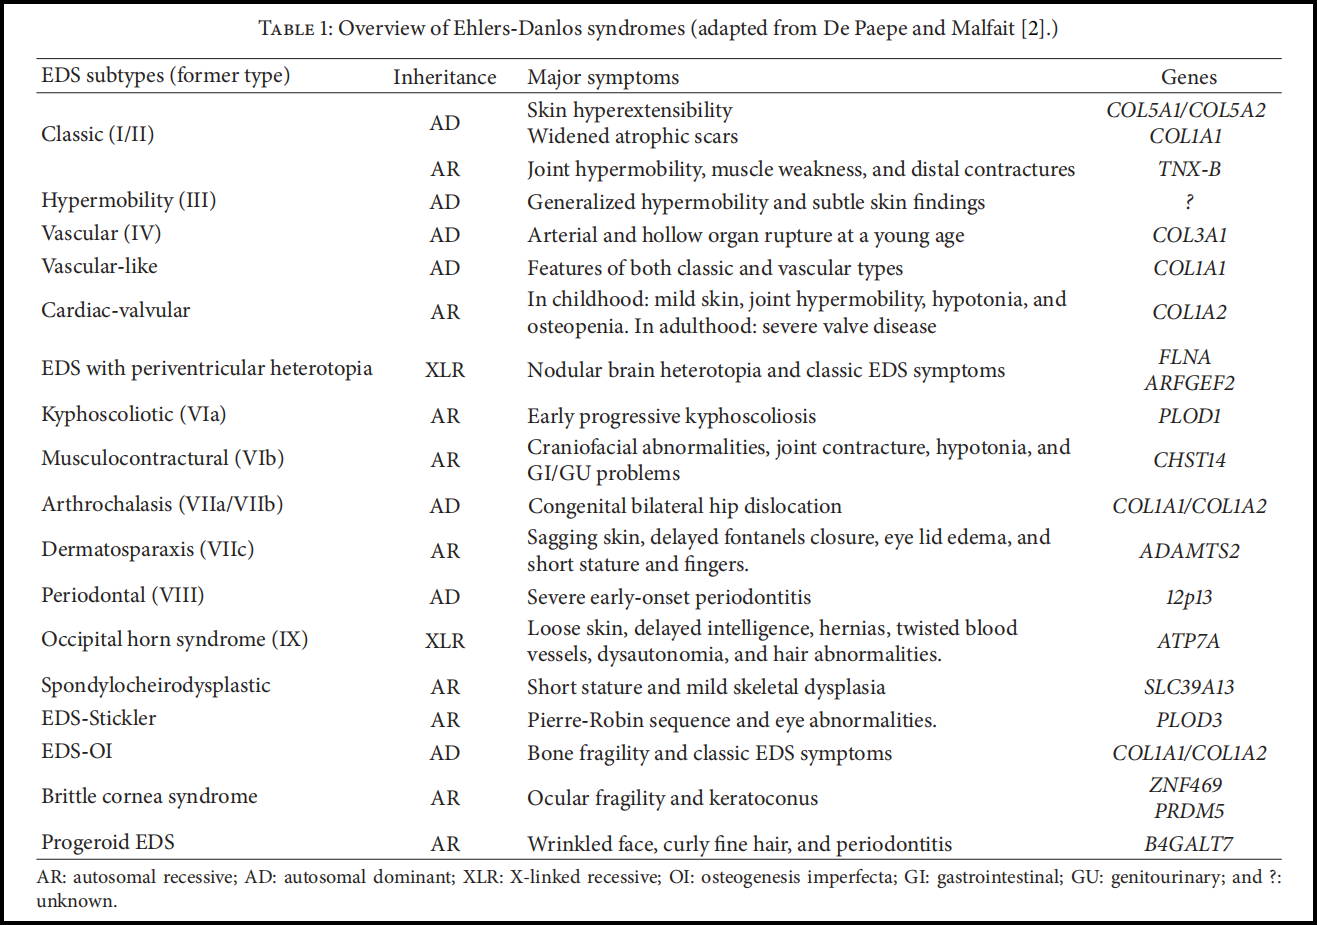

- 注意上面说到的不同程度,这意味着有的患者症状较轻,有的患者症状较重。按照病症和基因突变类型,埃勒斯-当洛斯综合征大概可以分为6种基本类型:

- 前三种呈常染色体显性遗传,后三种呈常染色体隐性遗传,大约有 90 % 90\% 90% 的患者都属于前两种类型,虽然会存在某些异样,但不至于影响到正常的生活,也不会危及生命。

- 1936年,埃勒斯-当洛斯综合征被正式命名,并确定了三个主要症状:关节必须过度弯曲,皮肤必须既具有弹性又异常脆弱,意味着皮肤容易受伤。这个听起来并不复杂的疾病并不是人们想象的那么平平无奇。在接下来的几十年中,医生们意识到有不止一种类型的埃勒斯-当洛斯综合征。具体有多少仍不确定。

- 1967年,一名外科医生根据27例不同症状的病例,表示有三种亚型。两年后,另一名医生在仔细研究了100名病人后提出了五种亚型。截至1988年,埃勒斯-当洛斯综合征已被发现有11种亚型。

- 可以确定的是,所有的亚型都与结缔组织有关,结缔组织包绕并支撑着我们的内部器官。连接肌肉和骨骼的肌腱与韧带,以及主要血管的管壁都是由结缔组织构成的。胶原蛋白是结缔组织中最重要的蛋白质,而埃勒斯-当洛斯综合征会以某种方式对胶原蛋白造成影响。